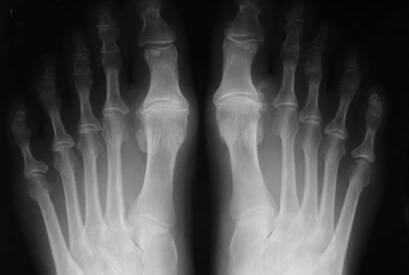

El Hallux Rigidus es una patología que impide la dorsiflexión de la articulación del Hallux (dedo gordo del pie).

Se caracteriza por una artrosis osteofítica, degenerativa y anquilosante de la primera articulación metatarsofalángica. El Hallux Rigidus es uno de los problemas más frecuentes del primer dedo del pie.

• Hipertrofia ósea: Este tipo de sintomatología se manifiesta como una deformidad abultada en la zona del primer metatarsiano. Habitualmente, tiende a confundirse con el famoso “juanete” por su parecido anatómico.

Debido a los cambios estructurales y a la pérdida de cartílago, se produce una disminución progresiva de la movilidad en la primera articulación metatarsofalángica, que va generando rigidez de una forma progresiva.